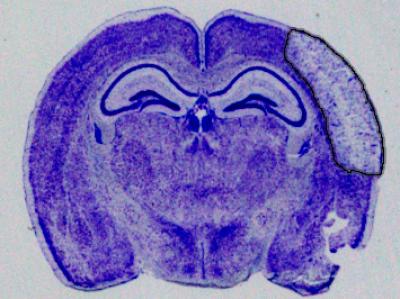

In a study published today in the Journal of Experimental Medicine , researchers successfully used a new approach that significantly minimized brain damage caused by stroke in mouse models. The new approach works by targeting hemichannels--pathways that allow for the flow of chemical ions and small molecules--that are expressed by astrocytes, cells that play a protective role for neurons in the brain.

For the study, the researchers used a genetic approach that mutated the channel proteins, called connexins, in such a way that blocks the formation of hemichannels. This allows the astrocytes to protect the neurons, significantly reducing the size of the stroke injury in the brain. The researchers also used a molecule called Gap19 to block the hemichannels, in the same stroke model, which also resulted in smaller stroke damage. Together, the two approaches demonstrate that connexin hemichannel blockers could be used as a neuroprotective agent in stroke.

The researchers also attempted to mimic "real life" stroke conditions in the study, waiting two hours after the stroke occurred before administering the drug.